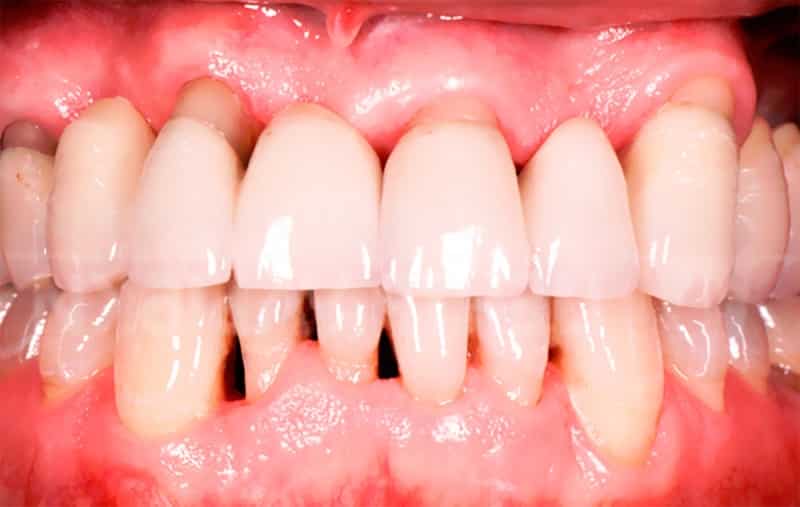

Пародонтоз — это заболевание, которое характеризуется прогрессирующим разрушением тканей, окружающих зубы. Врачи отмечают, что на начальных стадиях пародонтоз может проявляться незначительными симптомами, такими как покраснение и отечность десен. Однако по мере развития болезни наблюдаются более серьезные изменения. На фотографиях, иллюстрирующих это заболевание, можно увидеть отступление десен, образование карманов между зубами и деснами, а также появление зубного камня. Врачам важно подчеркнуть, что своевременная диагностика и лечение могут значительно замедлить прогрессирование пародонтоза и сохранить здоровье зубов. Визуальные признаки заболевания могут варьироваться, но в любом случае требуют внимания специалиста для предотвращения серьезных осложнений.

| Подвижность зубов | Зубы становятся шаткими, особенно на поздних стадиях заболевания. | [Изображение зубов с видимой подвижностью] |

| Изменение положения зубов | Зубы могут смещаться, расходиться, образовывать щели. | [Изображение зубов со смещением] |